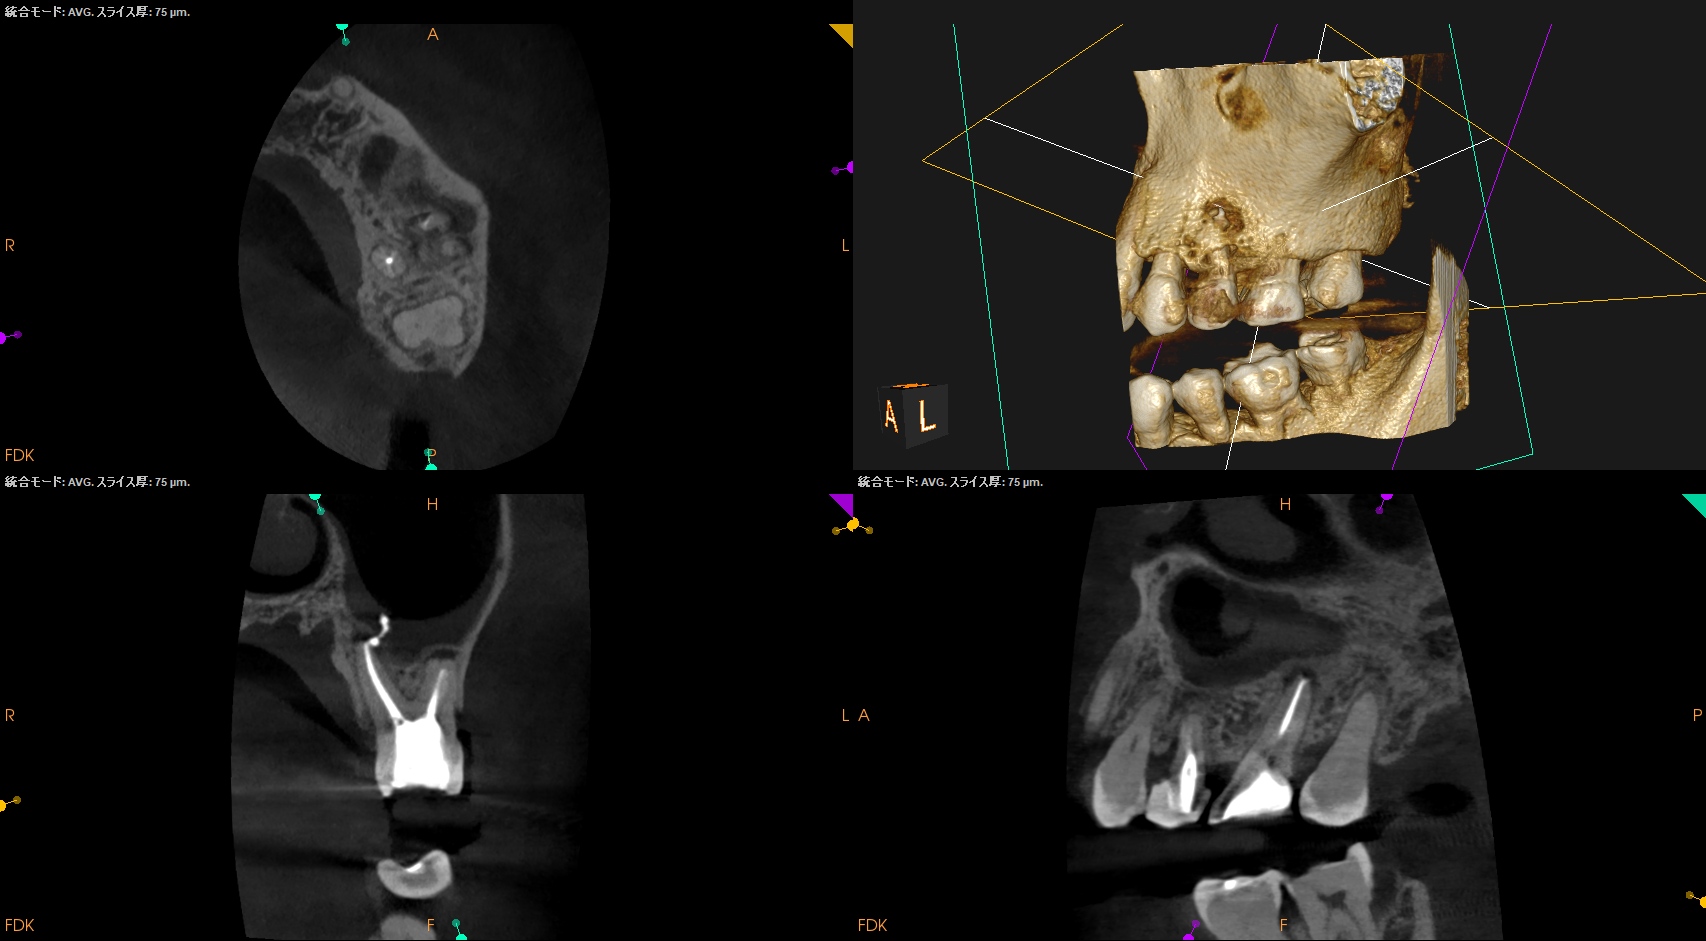

さておき、#13にも病変があるのがわかるので#13も分析した。

#13

#13は#14よりも大きな根尖病変がある。

ここも治療が必要だろう。

Pulp Dx: Previously initiated therapy

Periapical Dx: Symptomatic apical periodontitis

Recomended Tx: Re-RCT

おおよその作業長が類推できる。

が、いずれにしてもこの治療での最大のポイントになるのはMB2がどこにあるか?である。

MB2の根尖部にはCBCTで根尖病変があるからだ。